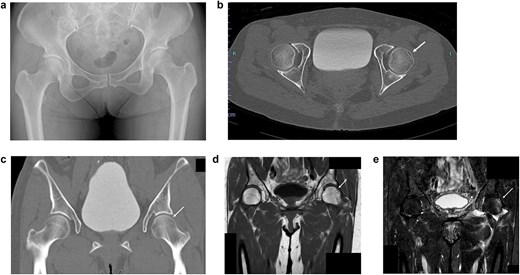

Post-reduction CT and magnetic resonance imaging (MRI) demonstrated concentric joint reduction without evidence of femoral head osteonecrosis (Fig. 4a–e). The patient was maintained non-weight-bearing for 4 weeks, followed by partial weight-bearing, and progressed to full weight-bearing by 10 weeks. At the 6-month follow-up, the patient reported only mild residual groin discomfort without any significant restriction in range of motion. Follow-up MRI revealed resolution of initial signal changes in the femoral head, and there were no new findings suggestive of osteonecrosis or cartilage degeneration.

Imaging results immediately after manual reduction. (a) Post-reduction pelvic radiograph confirming reduction. (b) Post-reduction axial CT image confirming reduction. (c) Post-reduction coronal CT image confirming reduction. (d) T1-weighted MRI showing a subchondral band-like low signal area. (e) STIR MRI showing diffuse high signal intensity beneath the subchondral lesion.